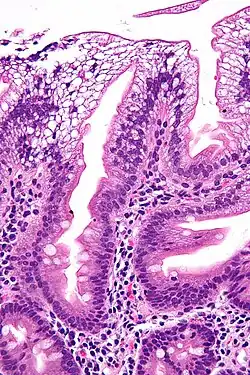

- gestörte Fettaufnahme aus dem Dünndarm mit Steatorrhoe

- Malabsorptionssyndrom